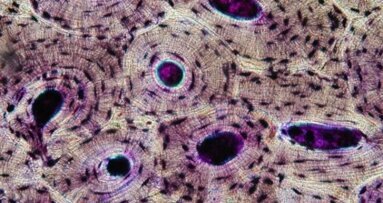

Ponadto, analiza piśmiennictwa przeprowadzona przez autorów wskazuje na coraz szersze zastosowanie kości allogennej z dobrymi rezultatami klinicznymi. Ważne wydaje się również z punktu widzenia gojenia przeszczepów, wspomaganie procesów osteogenezy przez miejscowe zastosowanie PRP (Platelet Rich Plasma).4 Potwierdzeniem powyższych mogą być badania Acocelli i wsp. W grupie 16 pacjentów z atrofią wyrostków zębodołowych użyto 18 bloczków allogennej kości świeżo mrożonej. We wszystkich przypadkach odnotowano prawidłową przebudowę, unaczynienie i konsolidację augmentatów, co potwierdzano badaniami histologicznymi. W nowoutworzonej kości umieszczono po ok. 6 miesiącach 34 implanty, co ciekawe – wprowadzono je z minimalnym momentem obrotowym 40 Ncm. W okresie obserwacji 18-30 miesięcy nie odnotowano utraty żadnego z implantów. Autorzy podkreślają słuszność zastosowania kości ludzkiej świeżo mrożonej jako alternatywy dla przeszczepów autogennych.5

Wyniki uzyskane przez Lee i wsp. podkreślają efektywność użycia allogennych bloków korowo-gąbczastych. Autorzy przeprowadzili doświadczenia w augmentacji wcześniej wytworzonych mechanicznie defektów w kości sklepienia czaszki królików nowozelandzkich. U każdego z 9 zwierząt wytworzono po 4 ubytki o średnicy 8 mm i następnie wprowadzano bloczki kości: gąbczastej, korowo-gąbczastej i korowej. Obserwacje przeprowadzano po 4, 8 i 12 tygodniach od implantacji. W analizach CT i histologii znamiennie najwyższy stopień tworzenia się nowej kości wykazały właśnie bloki korowo-gąbczaste.6

Także zespół badawczy Contara przedstawił interesujące i ważne wyniki analizy porównawczej w stosowaniu kości auto- i allogennej do rekonstrukcji atroficznych wyrostków zębodołowych. Okres obserwacji wyniósł 9 miesięcy po augmentacji obu form kości. Próbki kości pobierano trepanami z miejsc donorowych oraz kontrolnych u tego samego pacjenta. Następnie próbki poddawano analizie histologicznej, która wykazała porównywalne rezultaty w konsolidacji przeszczepów auto- i allogennych oraz w tworzeniu się nowej tkanki.7